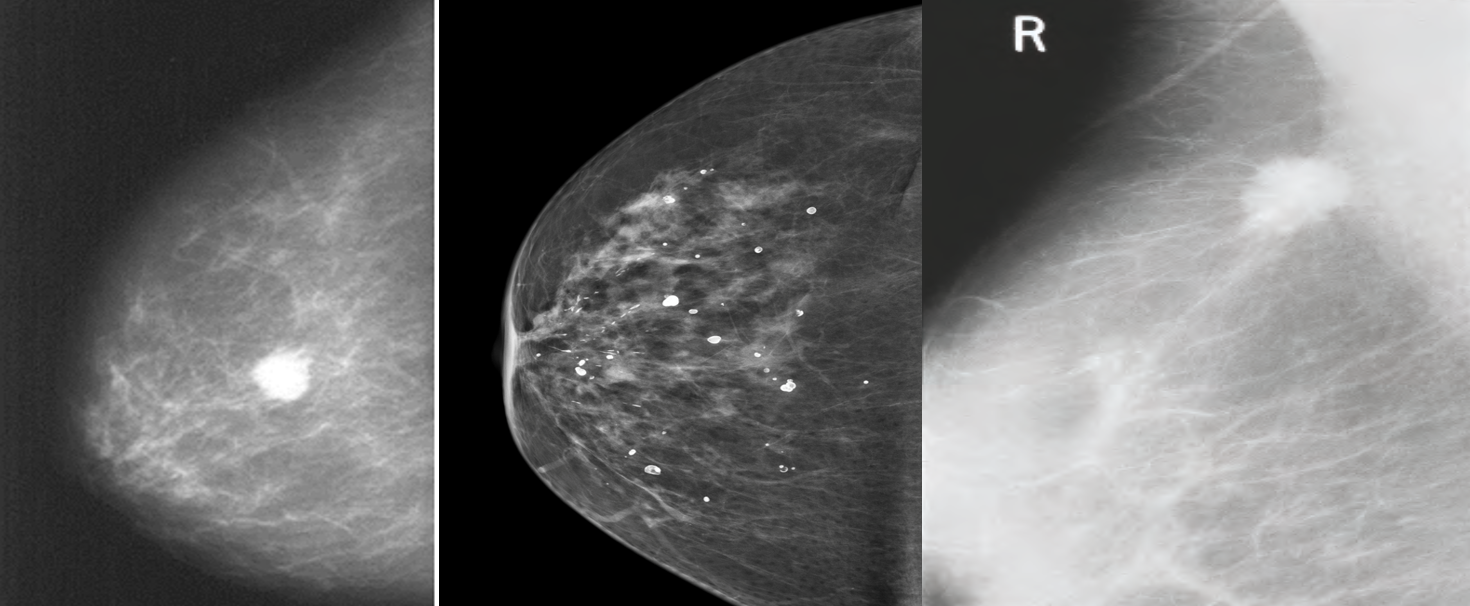

Abnormalities: architectural distortion, nodularity, mass, stellate lesion, microcalcifications, skin retraction, nipple changes and duct changes.

- Calcifications ranging from:

- benign involutional changes to suspicious

- suspicious micro-calcifications:

- pleomorphic, clustered, linear or branching (spiculated)

- Benign calcifications tend to be larger, more regular, white spots or flecks

Mammogram showing: (B) Benign calcifications (C) a carcinoma.